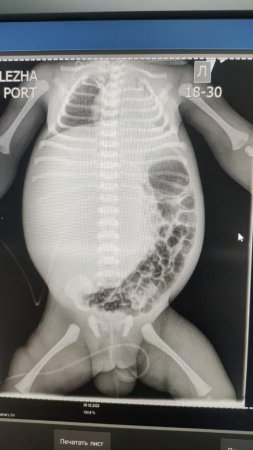

Гигантская опухоль печени занимала всю правую долю печени и была обнаружена сразу после рождения ребенка. 3 февраля трехдневный ребенок был переведен в Научный центр педиатрии и детской хирургии.

В течение пяти дней проводилась коррекция состояния и консервативное лечение. За короткое время объем живота увеличился с 38 см до 44 см. Образование сдавливало внутренние органы, в связи с чем ребенок находился на аппарате ИВЛ. Учитывая эти обстоятельства, мультидисциплинарно было решено провести оперативное лечение в срочном порядке.

№1 - Ангиография. Рентгенэндоваскулярная эмболизация правой печеночной артерии.